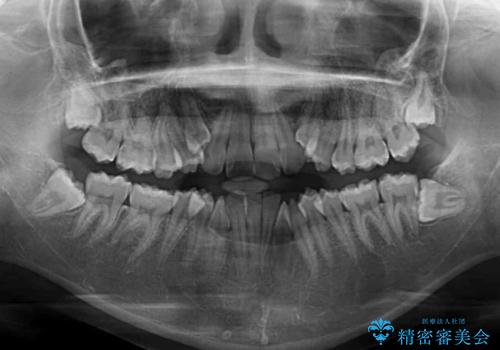

- 顕著な八重歯が気になるとのことで来院された患者様です。

インビザラインでの治療を希望されましたが、インビザライン単独では困難と判断されたため、補助装置や一部ワイヤー装置を用いて行うこととしました。

叢生が強いため、上下左右第一小臼歯4本を抜歯することとしました。